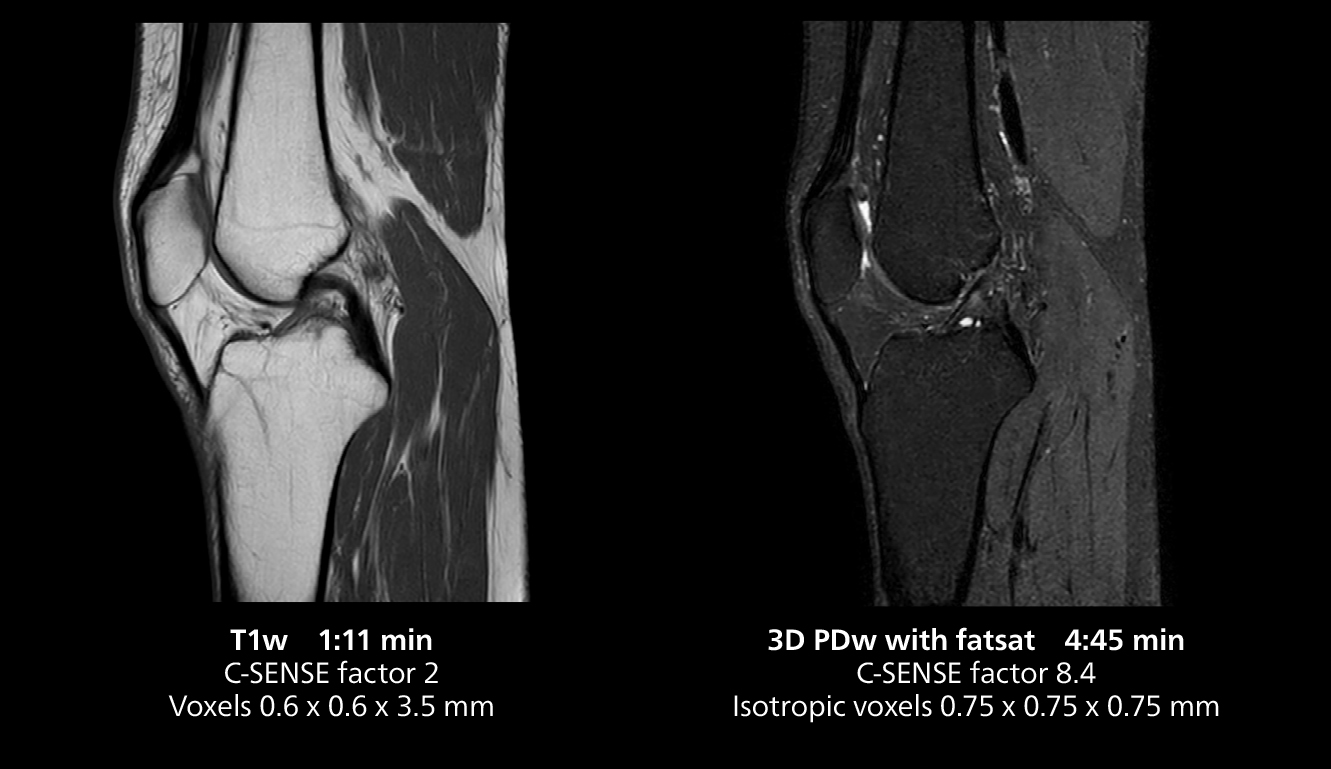

The isotropic high resolution 3D sequence in this MRI case allows for reformatting to obtain other orientations with high quality. Acquired on the MR 5300 system.

According to Dr. Gellée, the hospital conducts an average of four studies each hour, totaling about 40-45 patients per day on their MR 5300. Studies are read by approximately 50 radiologists in the Bordeaux area. Dr. Gellée is especially satisfied with the image quality of the MR system. "I obtain higher image contrast and more anatomical precision than I was used to,” she says. “When I am able to choose, I request that studies be done on this system, because I get better anatomical image quality. For example, in the knees, I can get great images of the meniscus. To me, it looks as pretty as 3T.”

“We have more speed in 3D sequences,” Dr. Gellée states. “With Compressed SENSE, we can replace two or three 2D scans withone high-quality 3D scan. High quality additional orientations are then obtained by post-processing of the 3D data set, thus saving scanning time.”